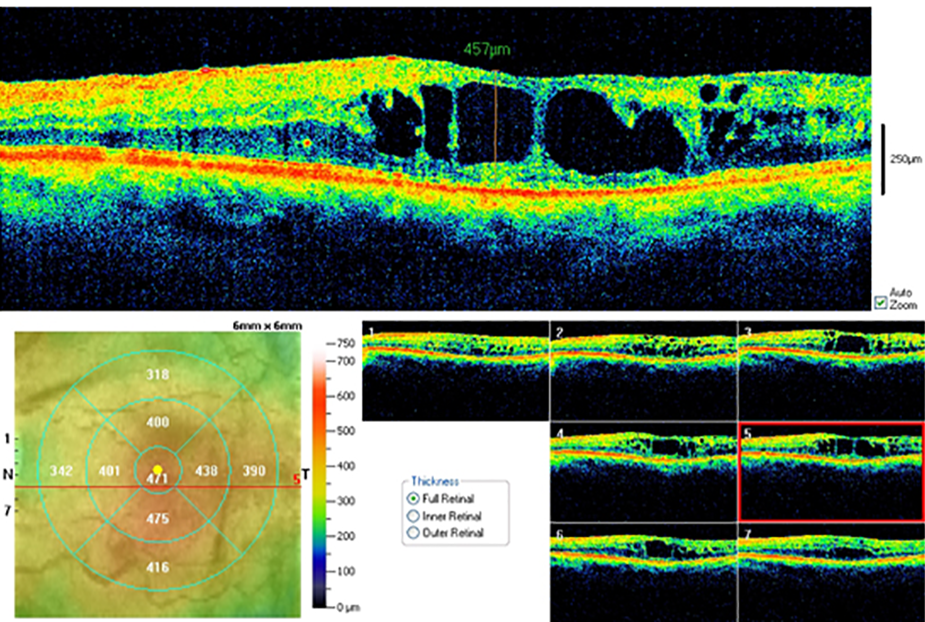

Tomografía de coherencia óptica (OCT, por sus siglas en inglés). La OCT es otra manera de observar en detalle la retina. Un equipo especializado analiza la estructura de la retina por medio de captura de imagenes en forma muy similar a tomar una fotografía y provee imágenes muy detalladas de su espesor. Esto ayuda al médico a detectar alguna fuga y medir la inflamación o edema de la mácula.